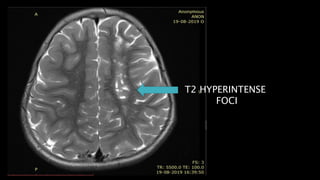

• #100 Chronic infarct Follows CSF signal

• #102 This is the saggital T1WI of a showing multiple oval T1 hypointensities in left centrum semiovale and frontal white matter in a in a child with homocystinuria

• #103 Which apppeaer hyperintense on T2WI

• #104 And shows signal suppression on FLAIR in the centre with marginal hyperintensity

• #105 There is no diffusion restriction on DWI and ADC map s/o chronic infarcts with glioenccephalomalacic changes.